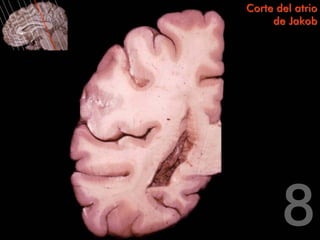

Corte del atrio

de Jakob

Centro oval del lóbulo

parietal

Surco del cíngulo

Circunvolución del

cíngulo

Surco lateral

Circunvolución                        Rodete del cuerpo

temporal superior                     calloso

Surco temporal

superior             Atrio del ventrículo

lateral

Circunvolución

temporal media      Surco colateral

temporal inferior

Tapetum

Centro oval del

lóbulo parietal                       Cola del núcleo caudado

Glomus coroideo

Radiación óptica                      Rodete del cuerpo

calloso

Fascículo

longitudinal inferior

Trígono colateral

Corte del atrio de Jakob Centro oval del lóbulo parietal Surco del cíngulo Circunvolución del cíngulo Surco lateral Circunvolución Rodete del cuerpo temporal superior calloso Surco temporal superior Atrio del ventrículo lateral Circunvolución temporal media Surco colateral Circunvolución temporal inferior

Corte del atrio de Jakob Tapetum Centro oval del lóbulo parietal Cola del núcleo caudado Glomus coroideo Radiación óptica Rodete del cuerpo calloso Fascículo longitudinal inferior Trígono colateral